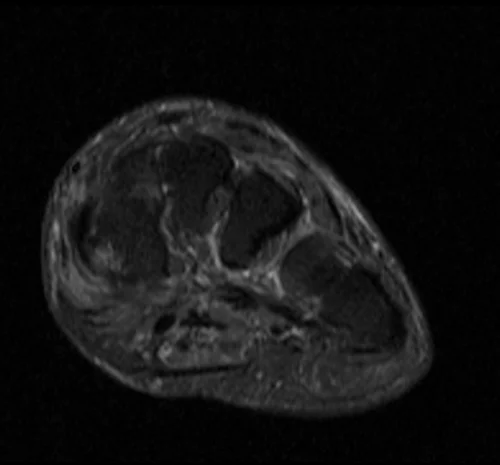

MRI FOOT AXIAL STIR IMAGE 1 - MRI